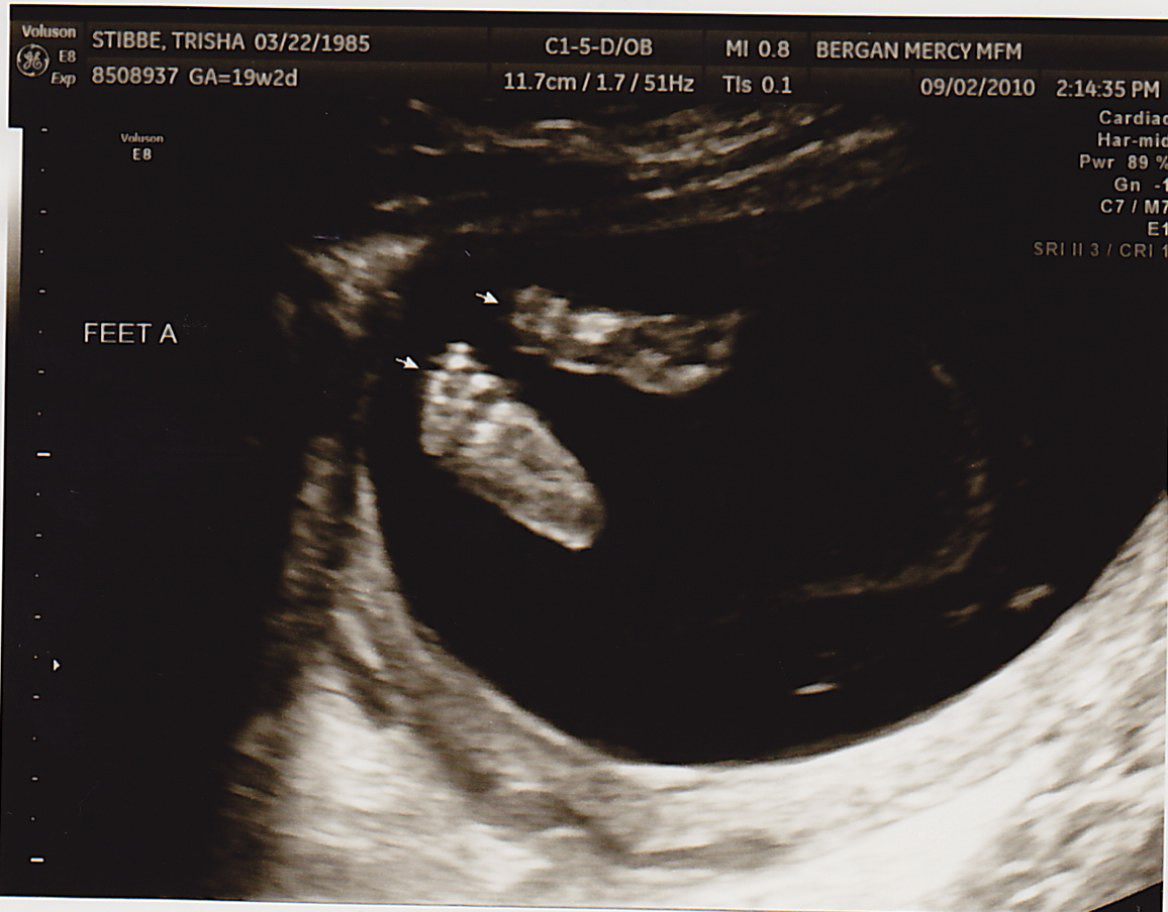

TODAY was a great appointment- we found out Baby B had a lot more fluid around himself!!! That means I didn’t have to have more fluid drained (at least for today). Baby A was 8oz and Baby B was 6oz. This is still good news, because two weeks ago Baby A was 6oz and Baby B was 4oz. As long as they’re both gaining the same amount of weight from here on out, we’re very positive everything will be okay. The difference between them just needs to continue to lessen.